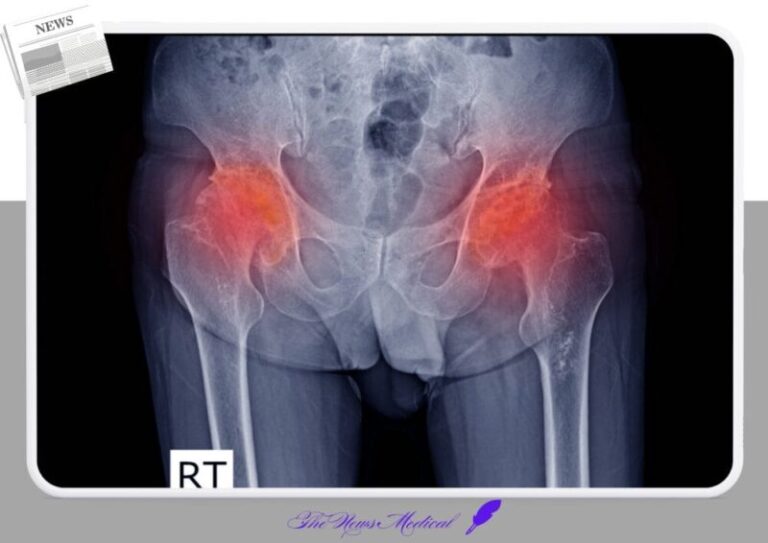

고관절 괴사, 초기 증상 없어 방치되기 쉬운 질환, 스테로이드 부작용? 장기 복용 환자 주의 고관절은 우리 몸에서...